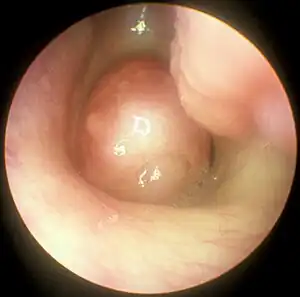

Pólipo nasal

Pólipo nasal, também chamado polipose nasossinusal (PN) e pseudotumor nasossinusal, são formações polipóides não neoplásicas, pedunculadas e edematosas observadas nas cavidades nasais e seios paranasais em decorrência de um processo inflamatório crônico da mucosa nasal.[1][4][5][6] Geralmente de ocorrência bilateral, seus sintomas incluem obstrução nasal constante com dificuldade para respirar pelo nariz, perda do olfato, diminuição do paladar e secreção nasal anterior e posterior. Cefaleia e dor facial podem ocorrer, mas não são frequentes.[1][4] Entre as complicações geradas por essa patologia, uma das principais é a sinusite.[7][2]

A etiologia é ainda obscura, mas supõe-se que a ocorrência de uma inflamação local persistente seja essencial para o desenvolvimento de pólipos nasais.[6] Todavia, as causas ainda são motivo de controvérsia e existem inúmeras teorias sobre o assunto descritas na literatura.[4] Sabe-se que ocorrem mais comumente entre as pessoas que sofrem de alergias, fibrose cística, sensibilidade ao ácido acetilsalicílico ou certas infecções.[8] O diagnóstico pode ser feito por rinoscopia anterior ou endoscopia nasal. Para avaliação da extensão da doença e sua anatomia, é recomendado a realização de tomografia computadorizada.[1][4]